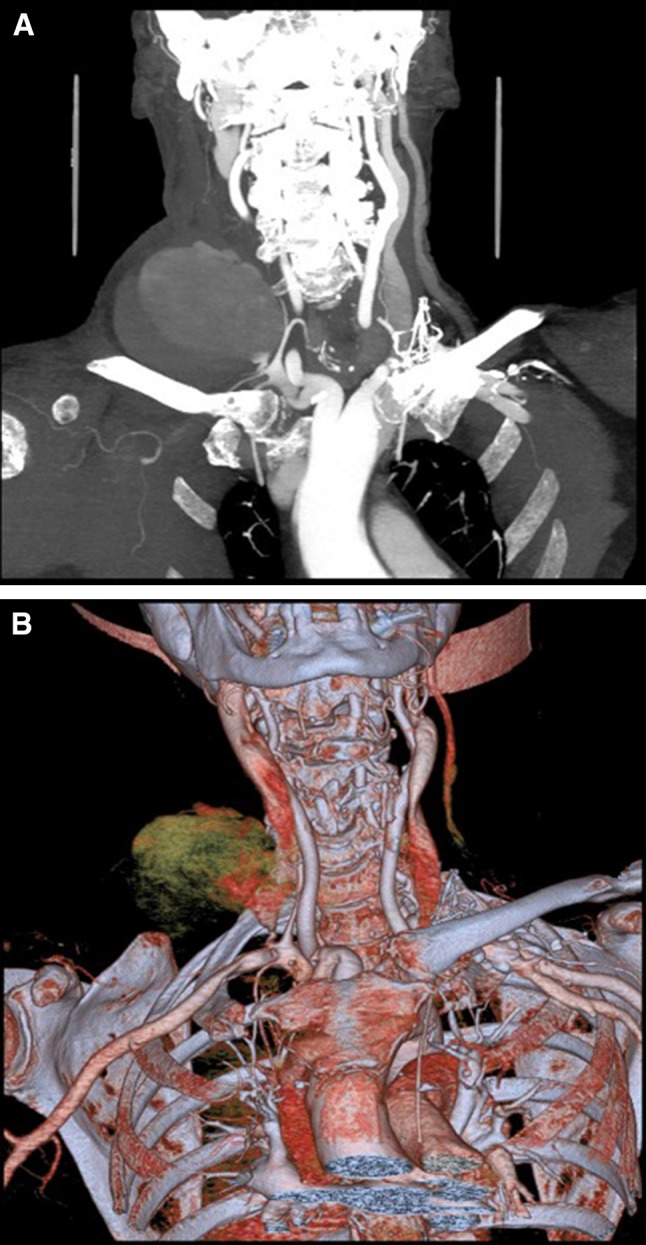

Central venous line insertion is a common medical procedure that can be complicated by inadvertent arterial placement of the catheter. This can be the cause of significant mortality and morbidity for the patient [1]. Treatment options include open surgical repair, compression, off-label use of percutaneous vascular closure devices (VCDs), and/or stent grafts. Some of the potential complications include bleeding, thrombosis, stroke, limb ischaemia, neurologic deficit, and death (Fig. 1). [1].

Fig. 1.

Coronal CT (A) and 2D reconstruction (B) of the upper chest and neck demonstrating large haematoma after inadvertent right subclavian artery puncture during right internal jugular vein line placement